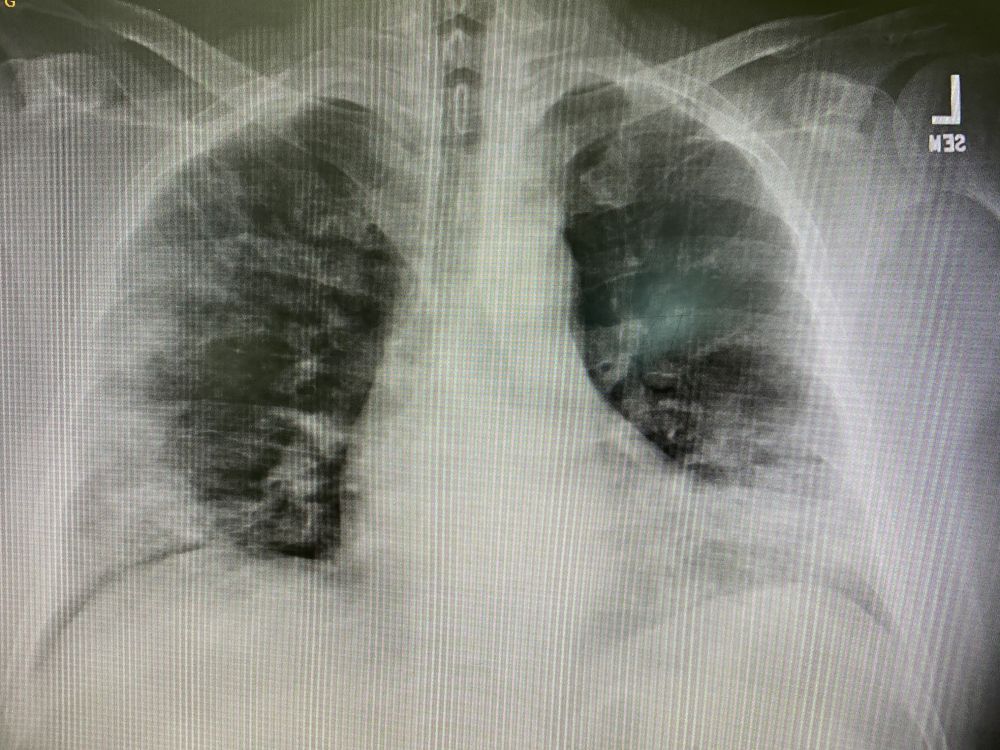

周四,病人没有家庭医生,来Urgent care就诊。体温高达103.2F(39.5C),还好血氧饱和度100%。病人血常规显白细胞轻微升高,有明显的淋巴细胞减少。做了快速新冠抗原检测,阳性!胸片可见明显的病变,好大一部分的肺都白了。原则上是病人的血氧饱和度低,才会建议病人去医院的,但是看到这么明显的胸片浸润灶,还是毅然决然的让病人去医院。很不幸的是,病人拒绝了,签了违背医嘱的AMA表格,坚持在家隔离观察,选择情况恶化了自己去医院急诊。

周一凌晨,噩耗传来。病人已经死在了家里。因为病人没有家庭医生,家属联系我们中心,帮忙签署死亡证明。